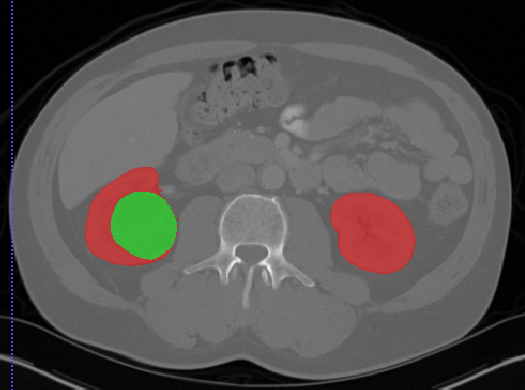

Kits19

| 名称 | 标注内容 | 类型 | 模态 | 数量 | 标签格式 | 文件格式 | License |

|---|---|---|---|---|---|---|---|

| Kits19 | 肾脏/肾肿瘤 | 分割 |